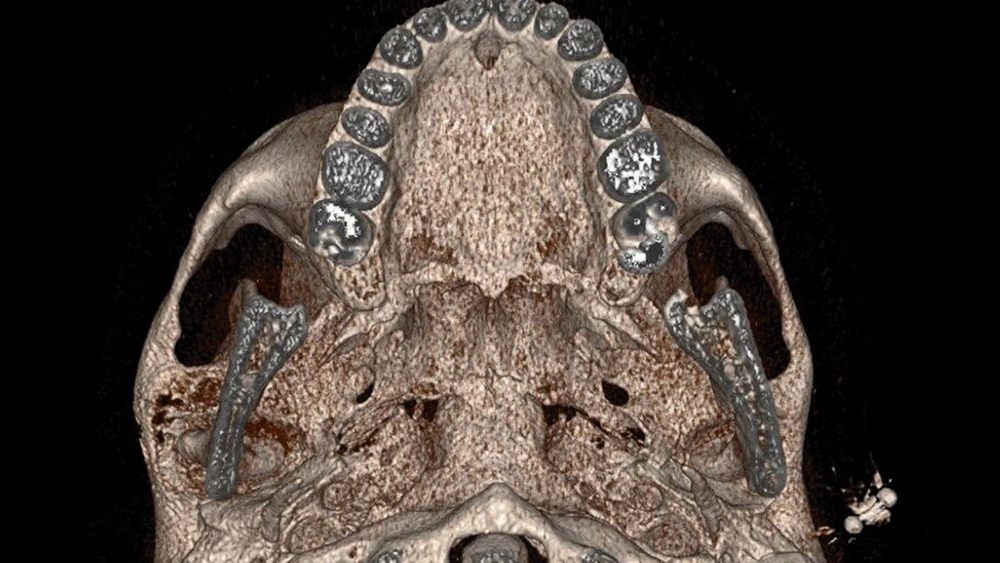

Im MRT und CT zeigte sich eine expansiv wachsende, überwiegend mattglasartige Knochenveränderung mit osteolytischen Anteilen und Unterbrechungen der Knochenstruktur, insbesondere in den unteren Partien nahe dem Kiefergelenk. Die Läsion war mit vermehrter intraossärer Kontrastmittelanreicherung assoziiert, was für eine fibröse Dysplasie spricht. Das Kieferköpfchen war abgeflacht, und es lag eine geringe Flüssigkeitseinlagerung im Kiefergelenk vor. In der Bildgebung fanden sich keine Hinweise auf eine Beeinträchtigung der umliegenden Foramina oder angrenzender Knochenstrukturen wie des Keilbeins (Abbildung 1).

Die Diagnose der CFD basiert in der Regel auf bildgebenden Verfahren, insbesondere der Computertomografie. Typisch ist dabei das sogenannte milchglasartige Erscheinungsbild des geflechtartigen Knochens, wie im vorgestellten Fall. Allerdings können die Läsionen sehr unterschiedlich erscheinen und auch sklerotische, zystische oder gemischte Strukturen aufweisen. Zu den differenzialdiagnostischen Überlegungen zählen unter anderem Meningeome, die Paget-Krankheit, niedriggradige Osteosarkome sowie verschiedene benigne fibroossäre Läsionen. Bei CFD-Läsionen mit maligner Entartung werden in der Bildgebung eine Destruktion der Kortikalis und eine Zunahme der Ausdehnung ins Weichgewebe beschrieben [Sun et al., 2014].